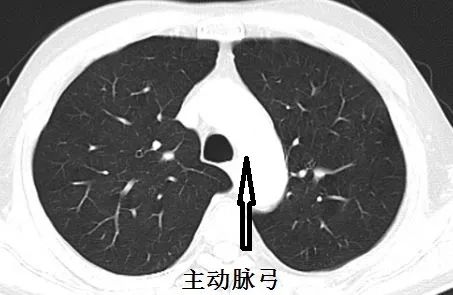

前不久会诊,遇到一个患者,CT如下:

平卧位,主动脉弓层面,没有气胸

隆突层面,少量气胸

中叶支气管层面,气胸增多

膈肌层面,气胸更多